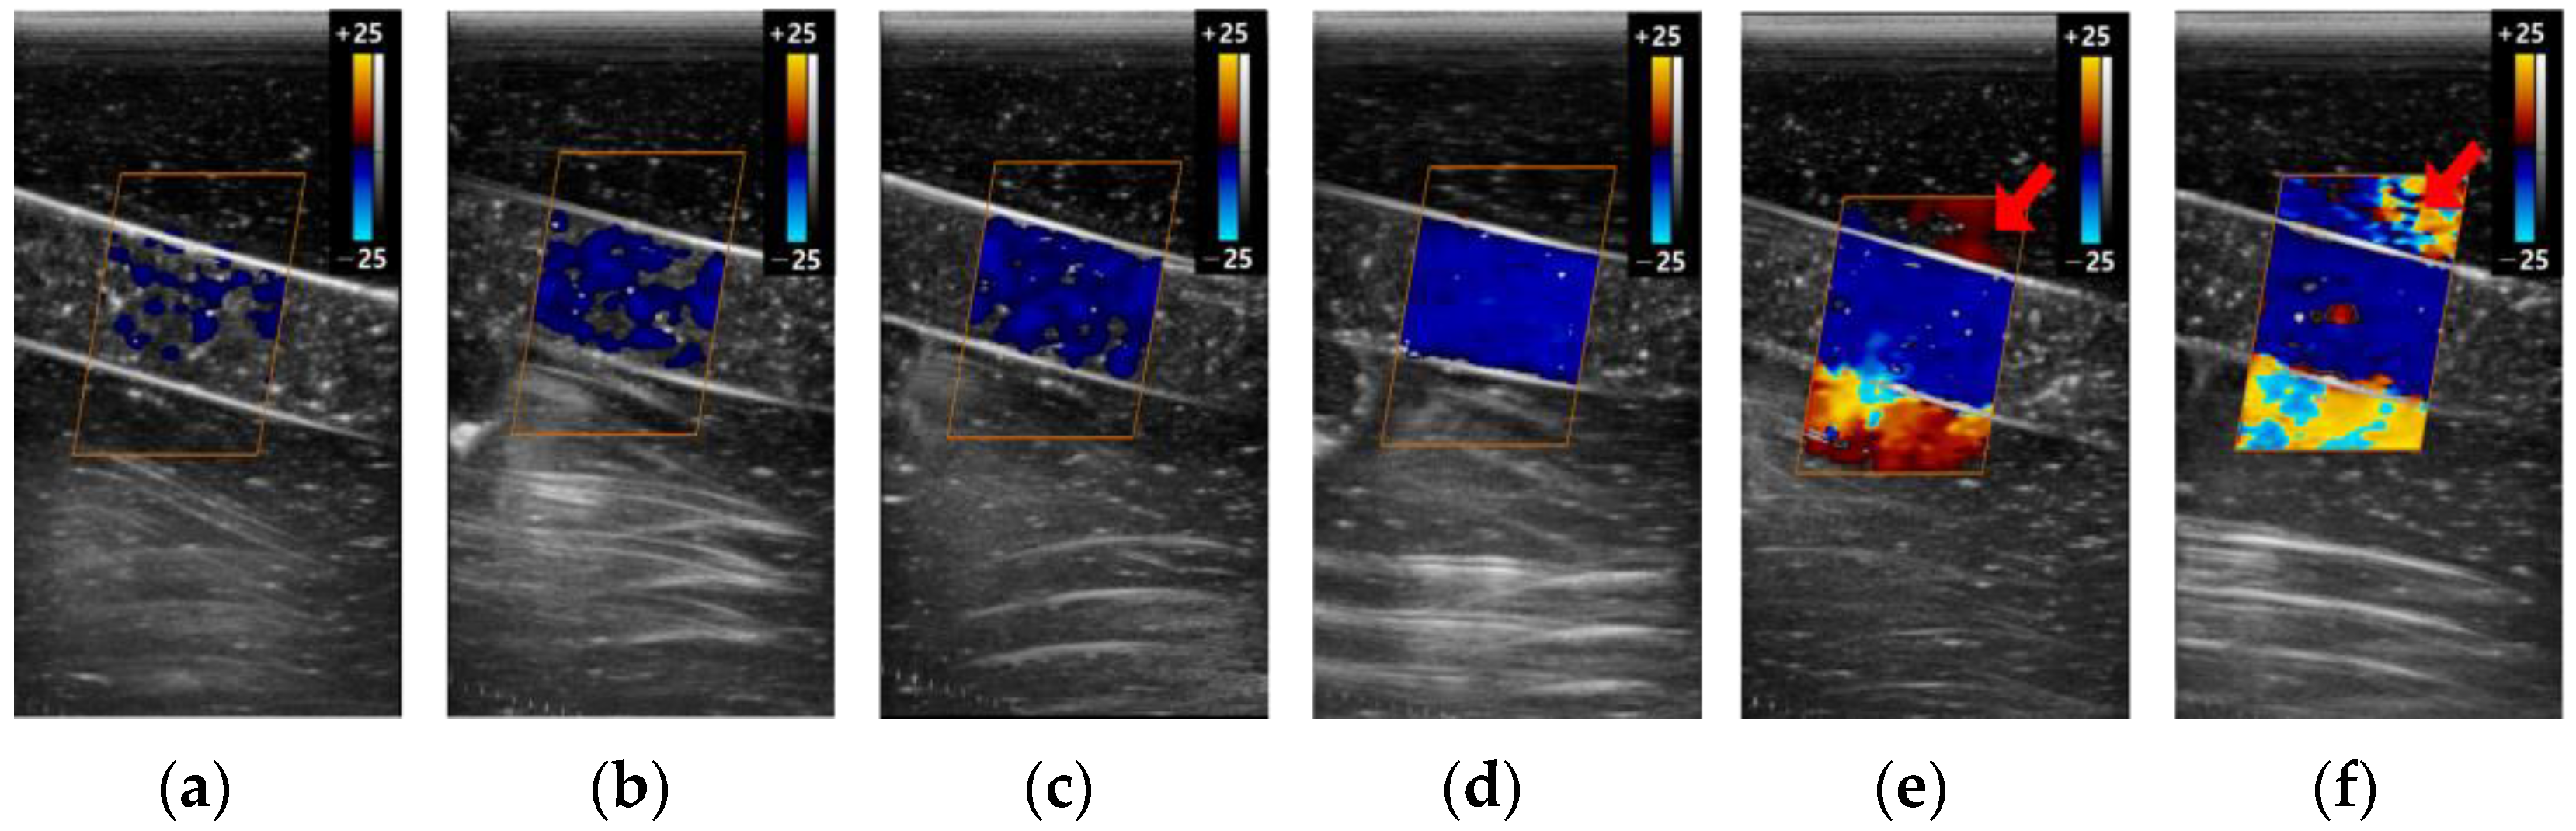

3.2. The Color Doppler Results

3.2.3. Gain